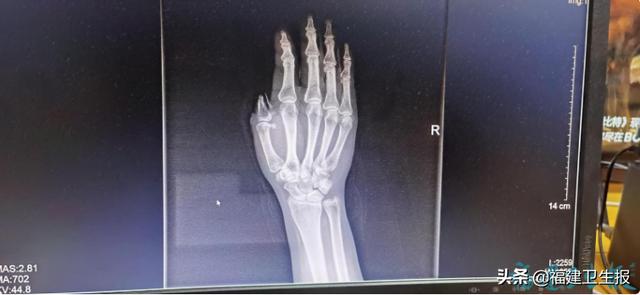

福州市第二医院手足显微外科主治医师刘晖介绍 , 经过检查 , 阿美右手大拇指Ⅲ度缺损 , 这意味着 , 如果只是清理伤口 , 她将永失拇指 。

文章插图